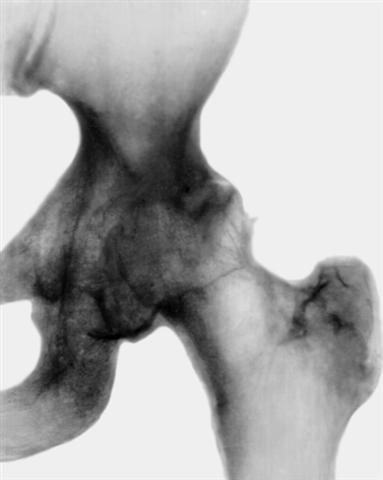

Рис. 1. Рентгенограмма левого тазобедренного сустава (прямая проекция) при диспластическом коксартрозе III степени: смещение головки бедренной кости наружу, уплощение суставных поверхностей и сужение суставной щели, остеофиты по краям вертлужной впадины, параартикулярный остеосклероз, множественные кистовидные образования в наружном отделе крыши вертлужной впадины и головке бедренной кости.